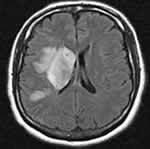

加拿大多伦多大学的研究人员最近发现了卒中引起脑细胞死亡的重要机制。他们发现,当脑细胞缺氧和缺乏重要的营养物时,受到影响的部分大脑,其脑细胞表面一种特殊通道——TRPM7被激活,启动了致命性连锁反应,脑细胞生产大量的自由基,而自由基又可导致TRPM7更活跃,产生自由基过多,引起脑细胞死亡。研究人员称干预这一连锁反应可能使脑细胞在缺乏氧和重要营养物的情况下存活3个小时以上。(Cekk 2003 ,115∶768-770)